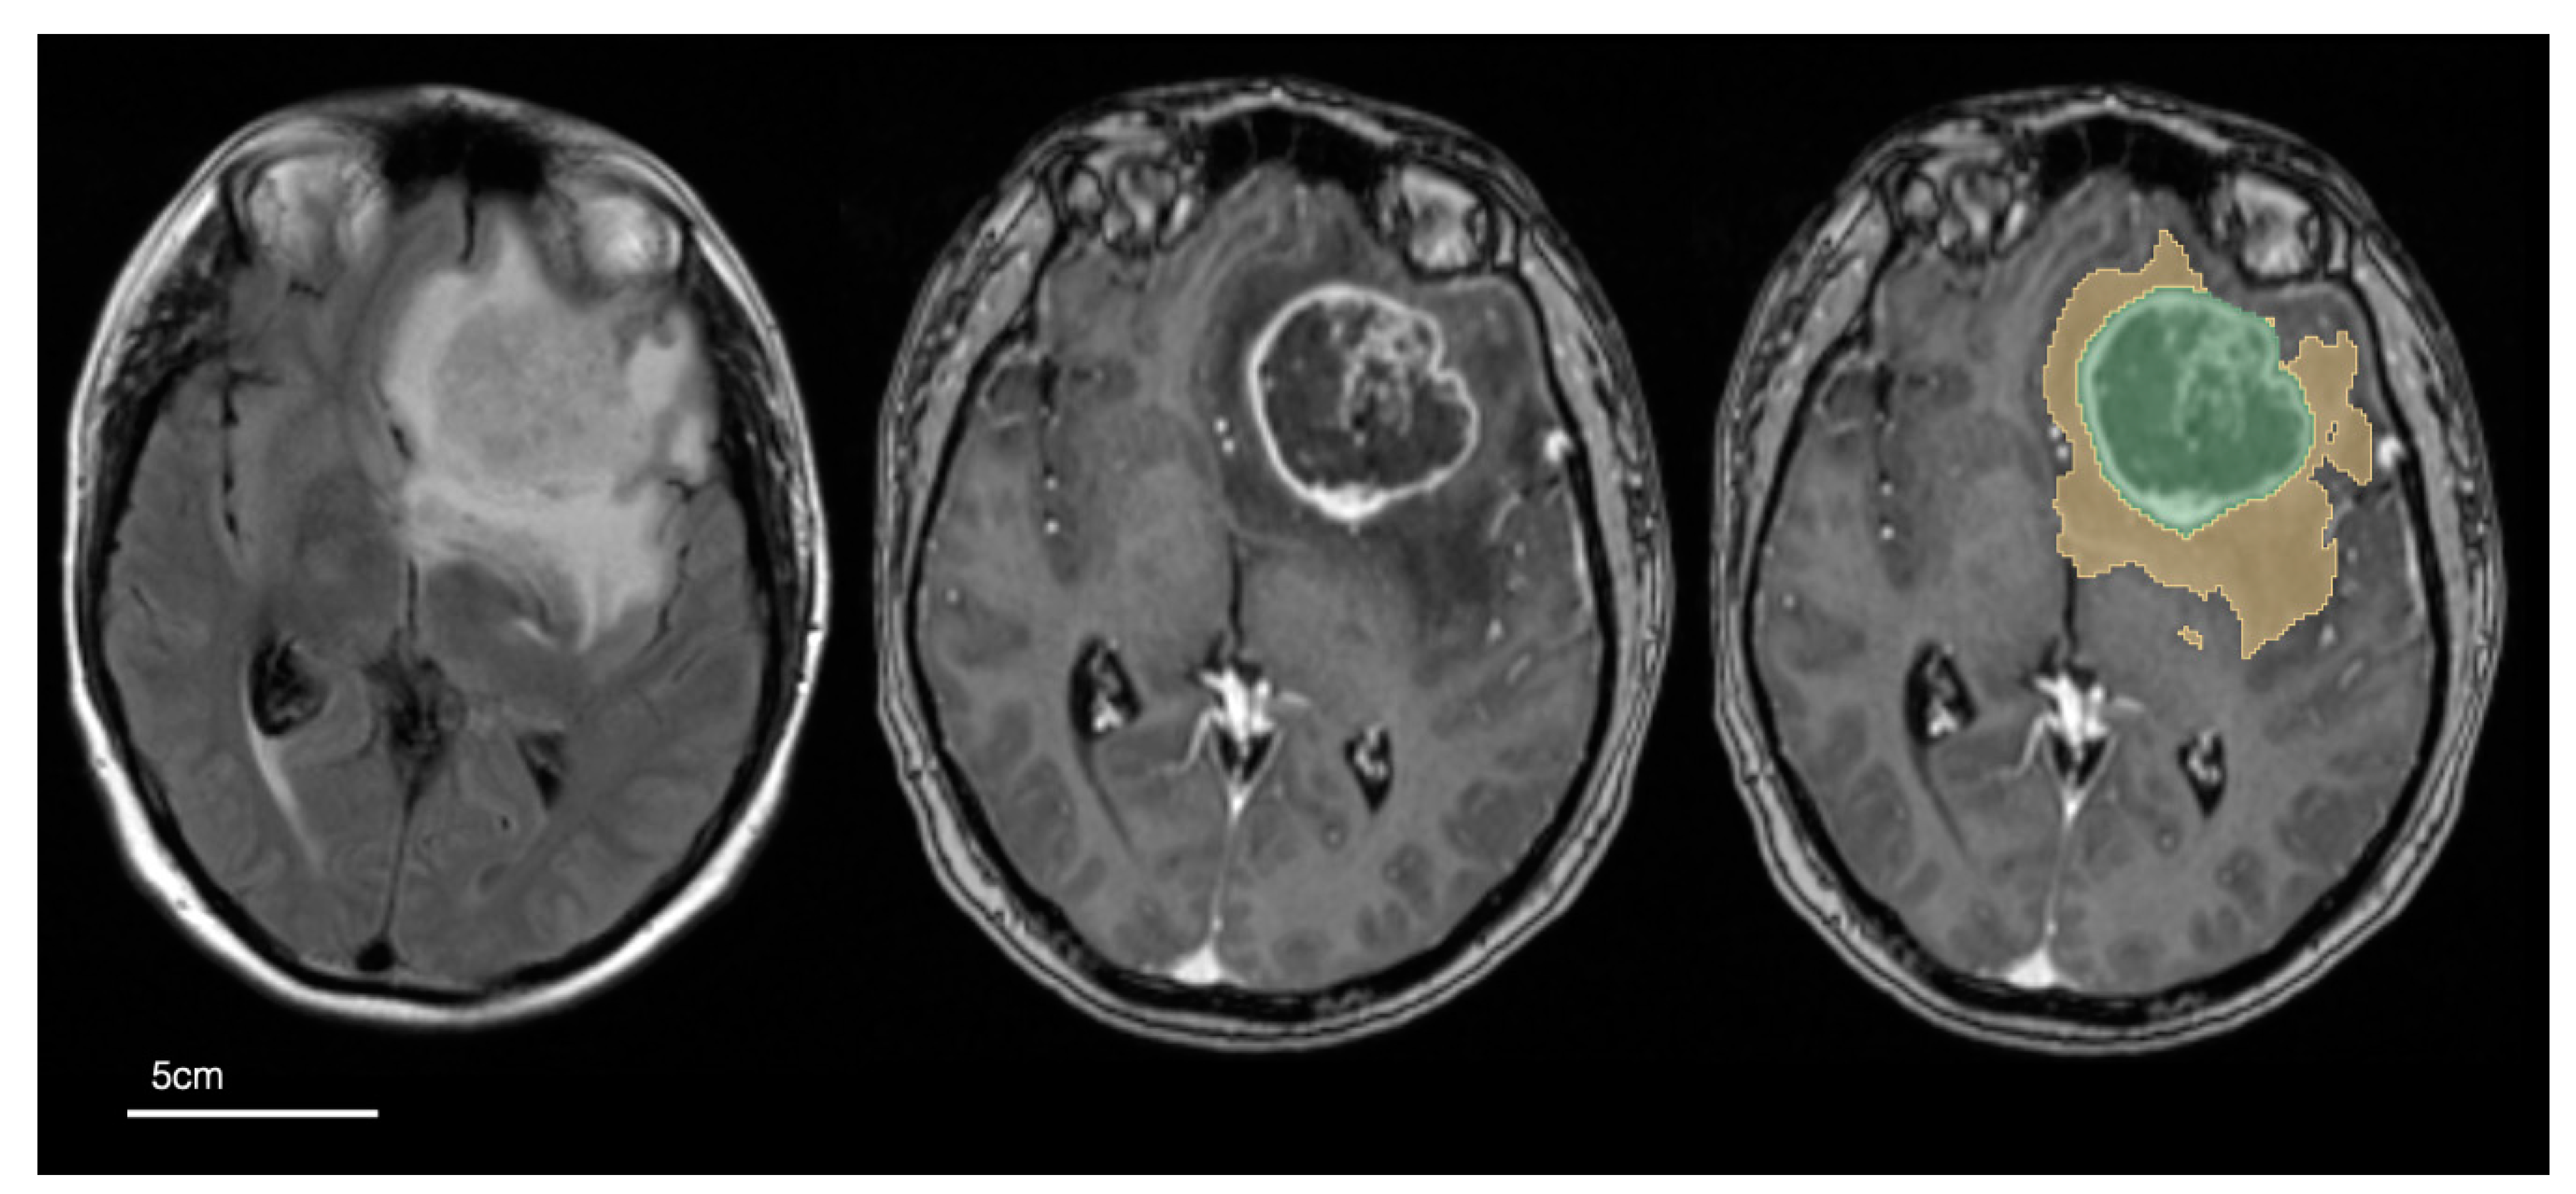

2.4. Image Pre-Processing and Tumour Segmentation

3.2. Segmentations and Univariable Cox Models of Tumour Size